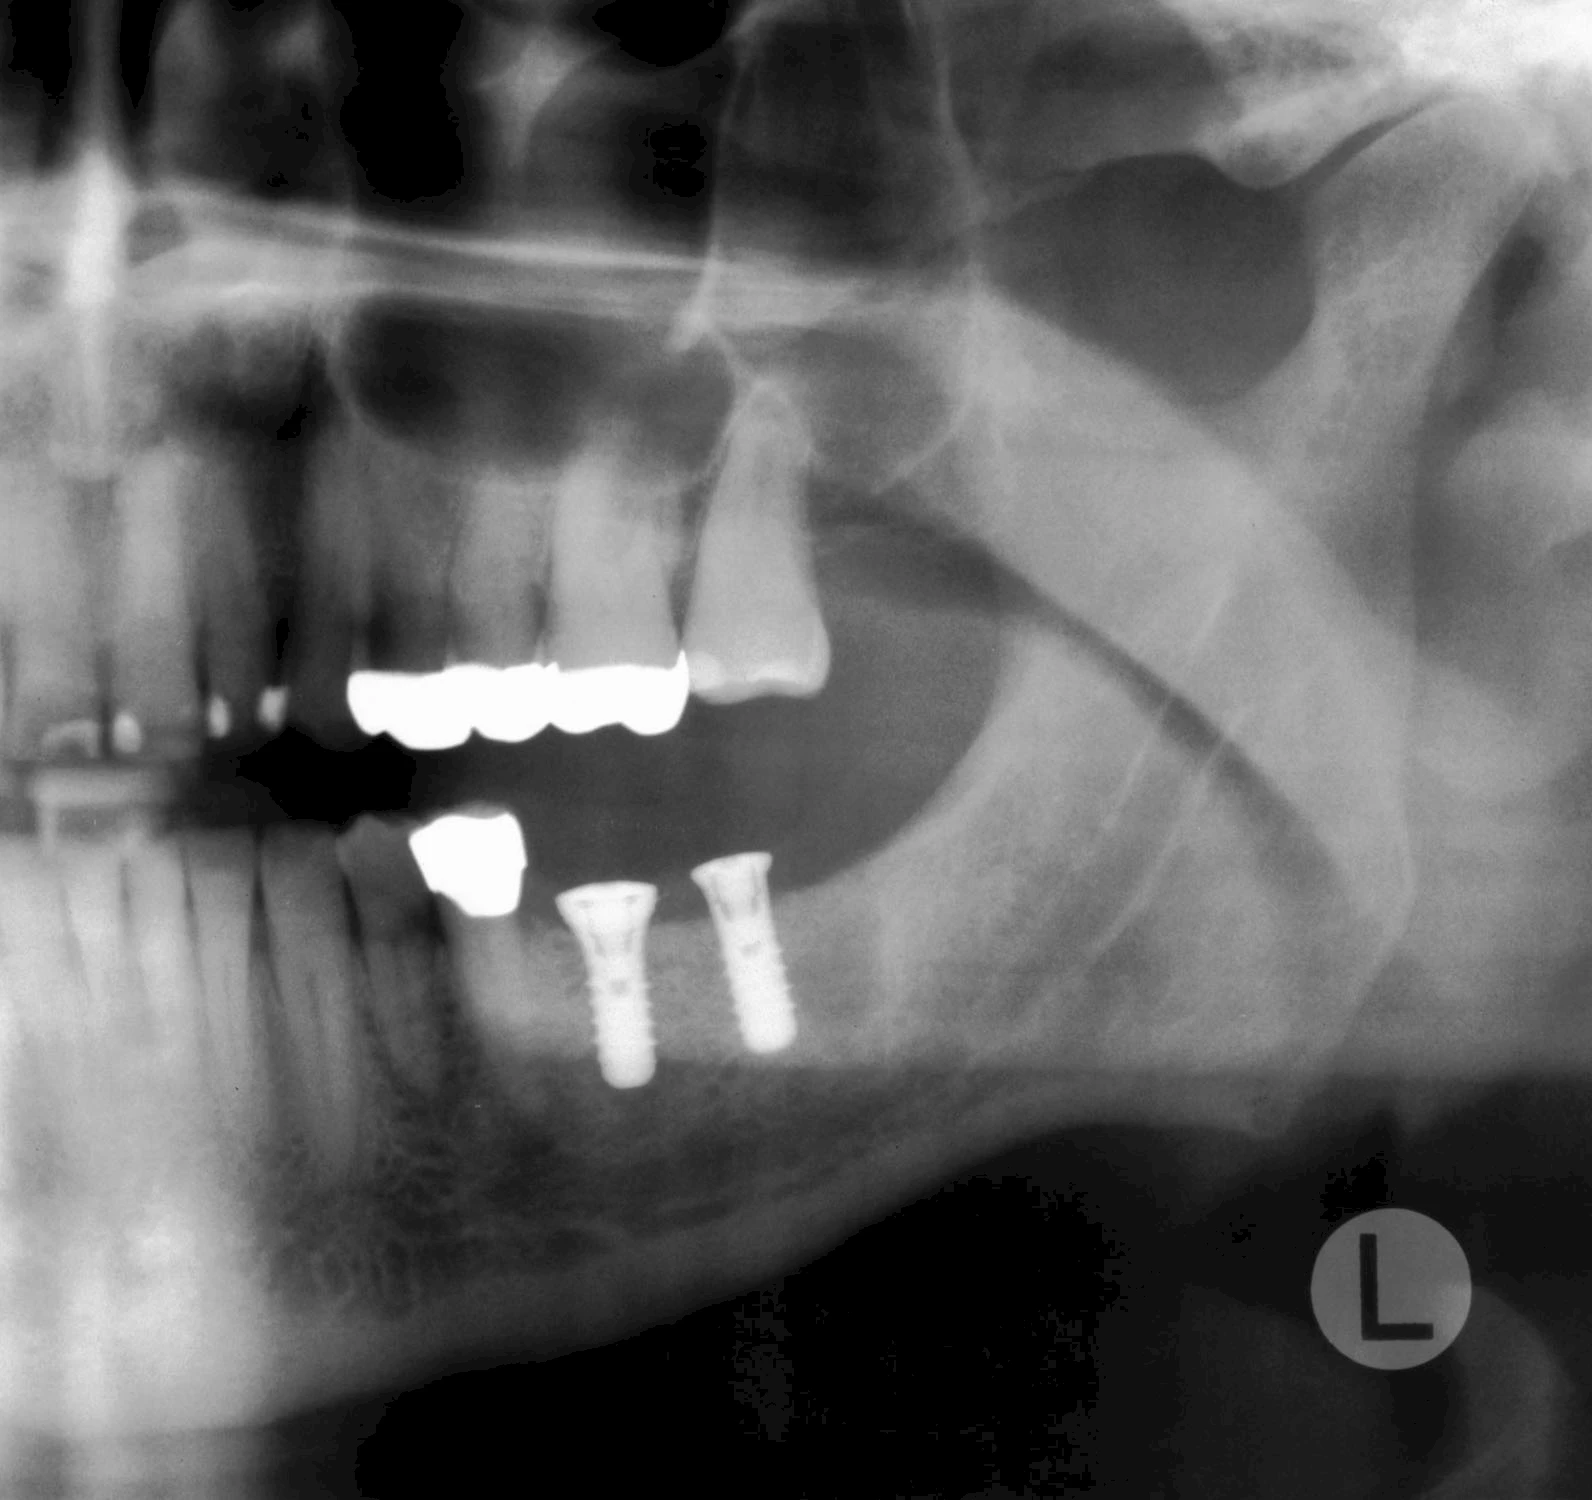

Damit Implantate an der richtigen Stelle im Kieferknochen platziert werden könen, gibt es heute vielfältige Möglichkeiten der Planung. In vielen Situationen kann die Erfahrung des Zahnarztes ausreichend sein.

Nicht selten ist jedoch auch eine technisch aufwändigere Vermessung im Vorfeld sinnvoll, z. B.:

- Wenn sich der Kieferknochen abgebaut hat

- Wenn der Nervverlauf im Unterkiefer beachtet werden muss

- Wenn die Ausdehung der Kieferhöhle im Oberkiefer beachtet werden muss

- Wenn wenige Restzähne keine gute Orientierung erlauben

In diesen Fällen kann die Planung mittels verschieden aufwendiger Röntgen-Techniken (Übersichtsaufnahme, DVT) ggf. unter Zuhilfenahme speziell angefertigter Planungsschablonen sinnvoll sein.